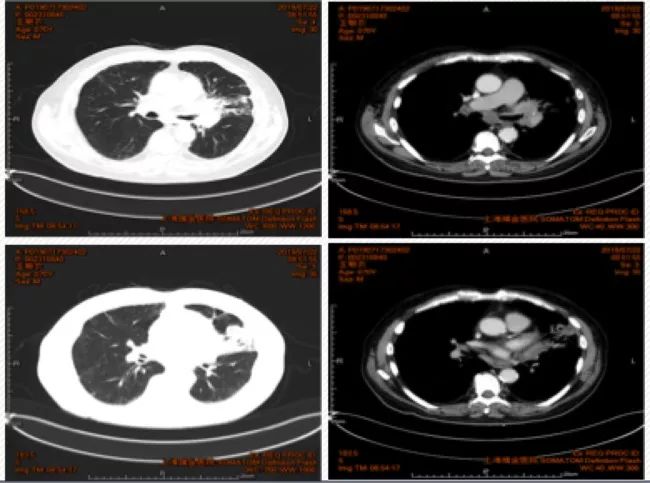

12. 治疗方案:继续白蛋白紫杉醇+卡铂+帕博利珠单抗治疗;经胸外科/放疗科MDT讨论:行同步放化疗,治疗结束评估是否可行手术治疗;2019年9月27日行第一次放疗定位。最新复查评估时间为11月13日,评估结果为SD。

图4. 2019年10月1日胸部CT